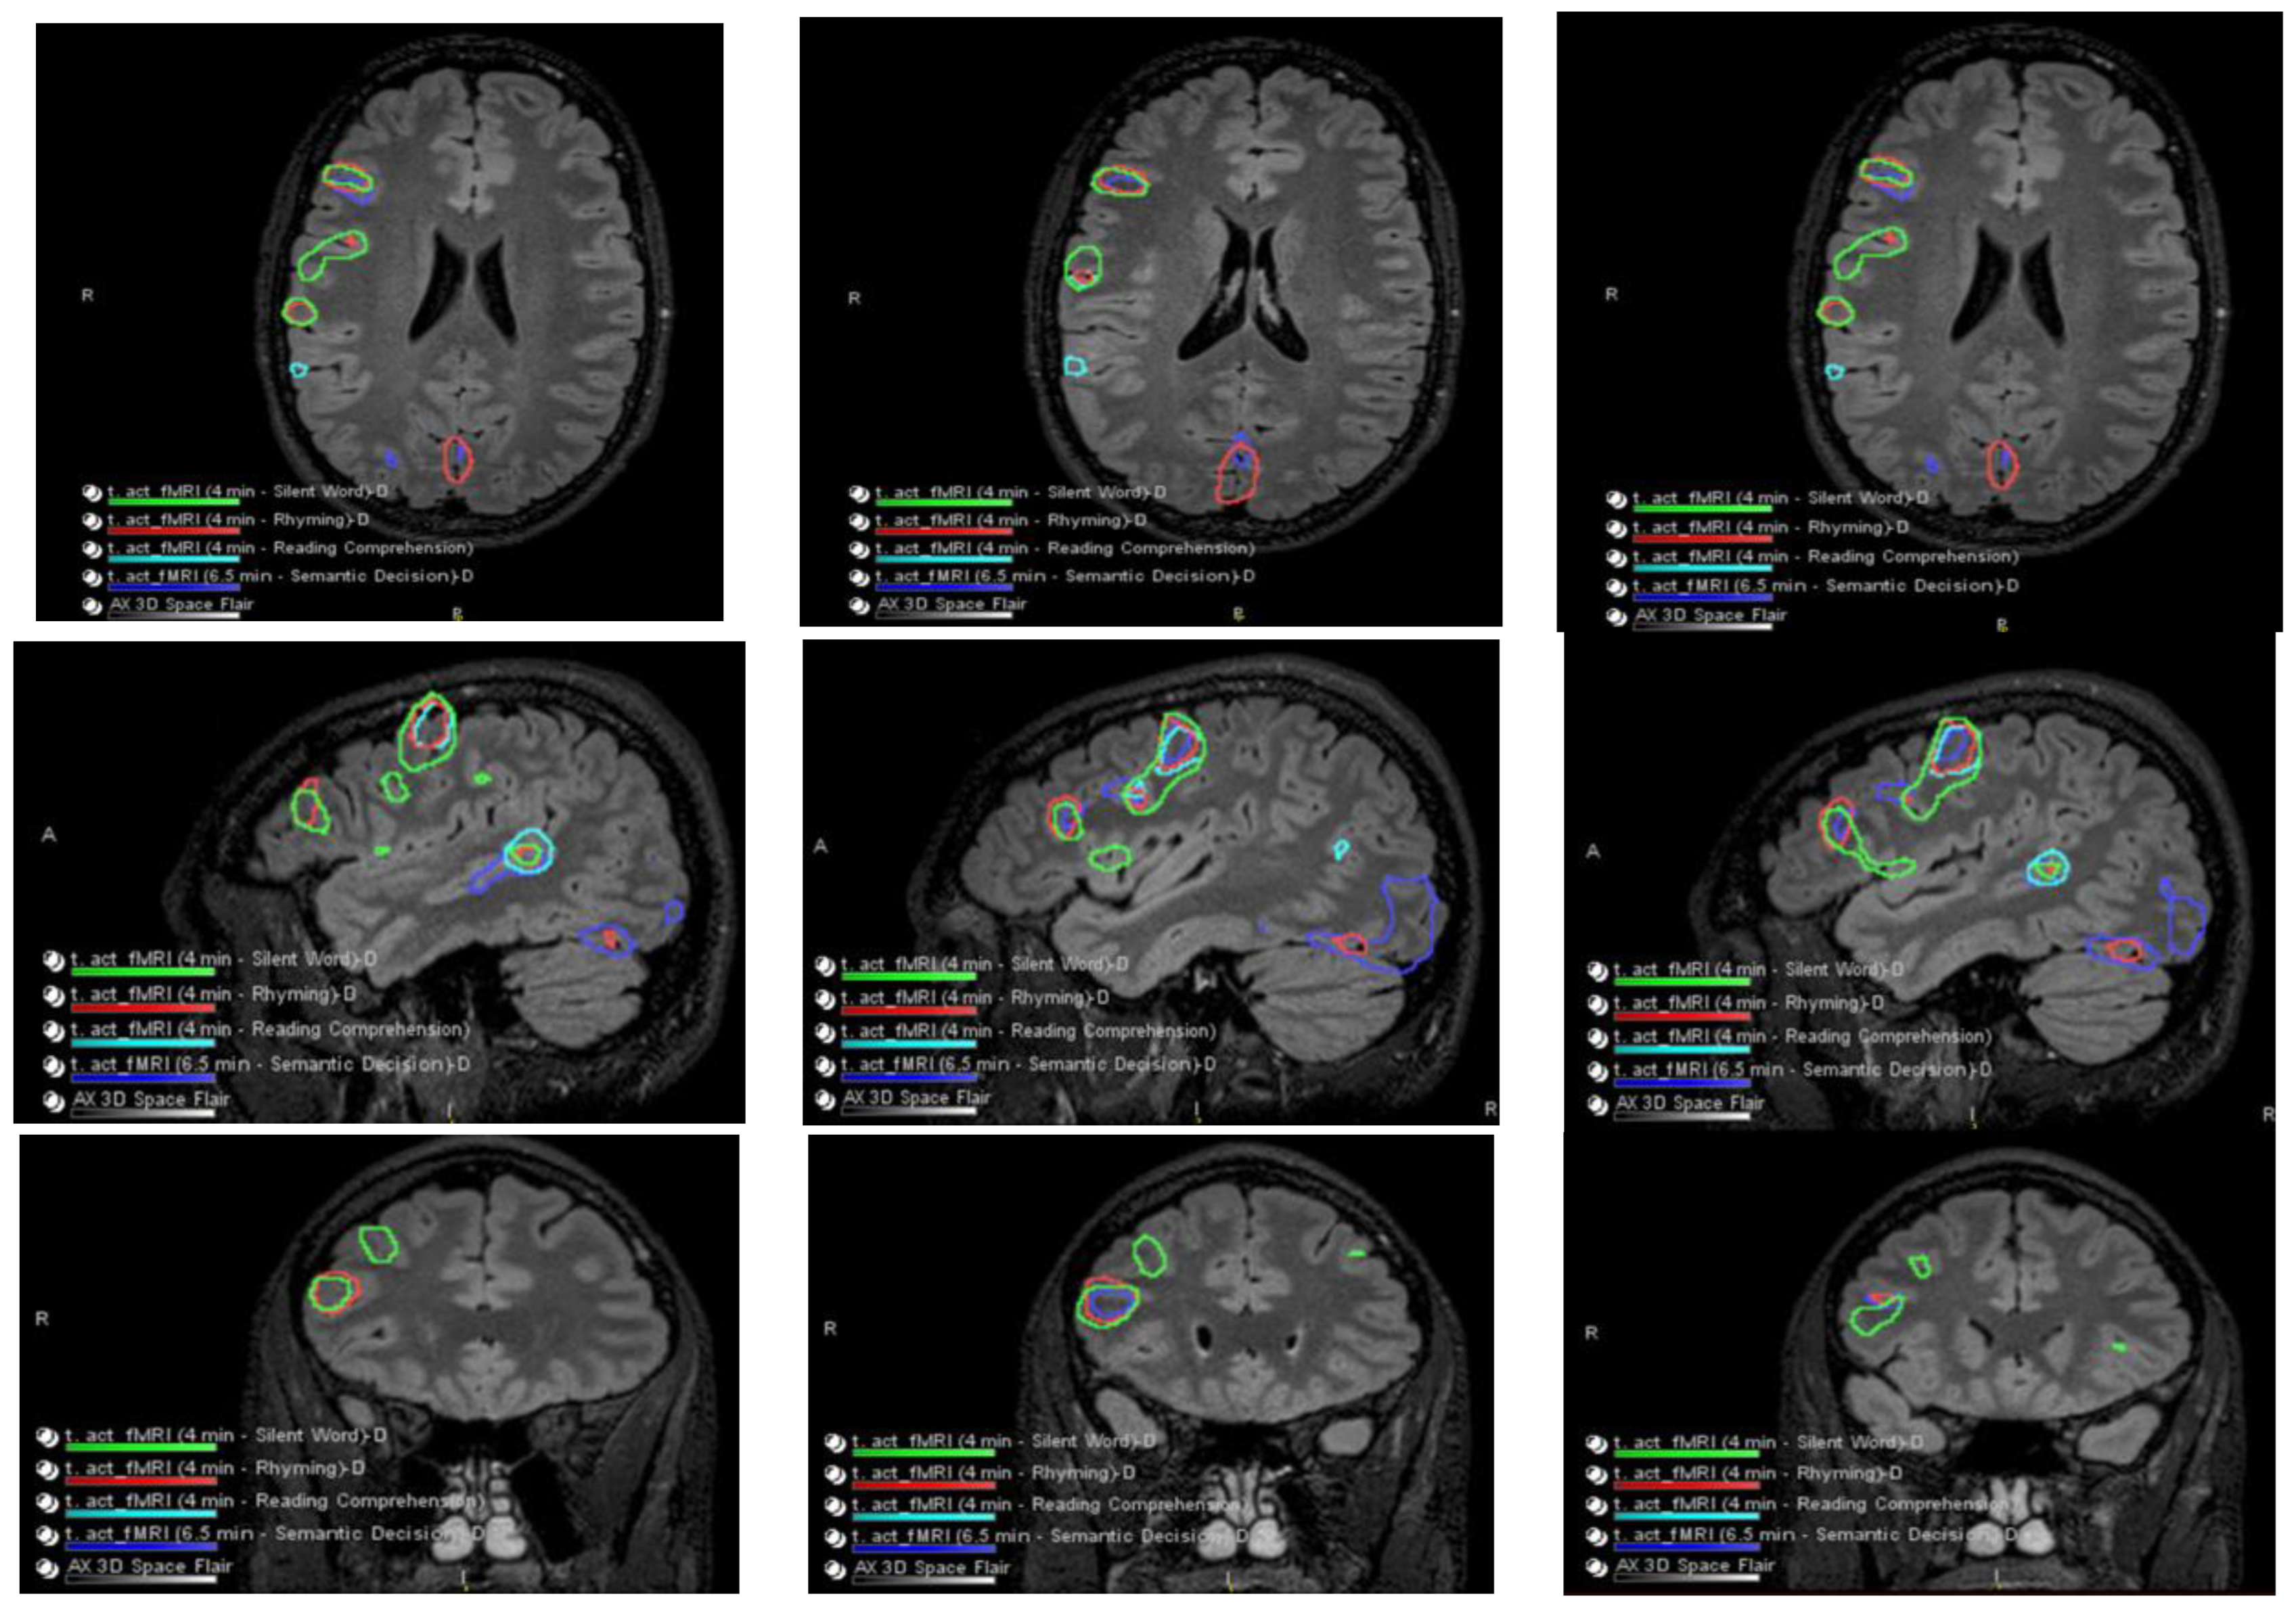

The patient had a functional MRI scan of the brain. This showed no change in the probable cortical dysplasia of the posterosuperior right temporal lobe at its junction with the angular gyrus. There was strong right cerebral hemispheric language lateralization. The right Wernicke area was just inferior to the presumed cortical dysplasia, although it was noted that language function could extend into the dysplastic cortical region with at least some language tasks (Figure 2 and Figure 3).

Figure 2.

Language and Verbal Memory fMRI Testing. There were no obvious perfusion abnormalities. During cerebrovascular reactivity (breath hold), there was no cerebrovascular reactivity abnormality evident.

Figure 3.

Co-localization of language-related activity with the silent word, rhyming, and reading comprehension tasks is also centered at the posterosuperior portion of the right pars triangularis. This is visualized on axial slides (ROW 1), sagittal slices (ROW 2), and coronal slices (ROW 3) suggestive of a right-sided Broca area. Other more posterosuperior right language-related activations are also seen with all 4 language tasks.

Language-related activation strongly lateralized to the right cerebral hemisphere with all four language tasks. The co-localization of activation centered at the posterior aspect of the right superior temporal sulcus with all four language tasks, which is suggestive of a right-sided Wernicke area (e.g., see overlaid summary maps axial sagittal coronal, respectively, in ROW 1).

With three of the four language tasks, areas of right Wernicke activation are very near each other in the right temporo-parietal-occipital cortex. These are within a centimeter, essentially abutting the inferior aspect of the adjacent presumed cortical dysplasia, although with the fourth (reading comprehension) task, language activation extends to/into the posterolateral aspect of the presumed cortical dysplasia (ROW 2). Of course, the volumes of these language-related activations as visualized on these maps are rather arbitrarily set by adjusting thresholds for sensitivity and specificity.

No appreciable left cerebral language-related activation was seen with three of the four tasks. With the fourth task, i.e., the silent word generation task, there was a small amount of homologous left-sided Broca area activation and a small amount of left dorsolateral prefrontal cortex activation.